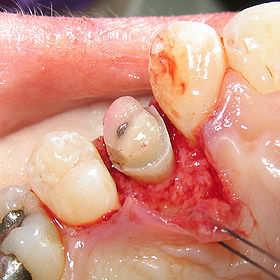

A palatal view of a maxillary premolar during a

crown lengthening procedure.

Crown lengthening is a surgical procedure performed by a dentist to expose a greater amount of tooth structure for the purpose of subsequently restoring the tooth prosthetically. This is done by incising the gingival tissue around a tooth and, after temporarily displacing the soft tissue, predictably removing a given height of alveolar bone from the circumference of the tooth or teeth being operated on. While many general dentists perform this procedure, they frequently refer such cases to periodontists.